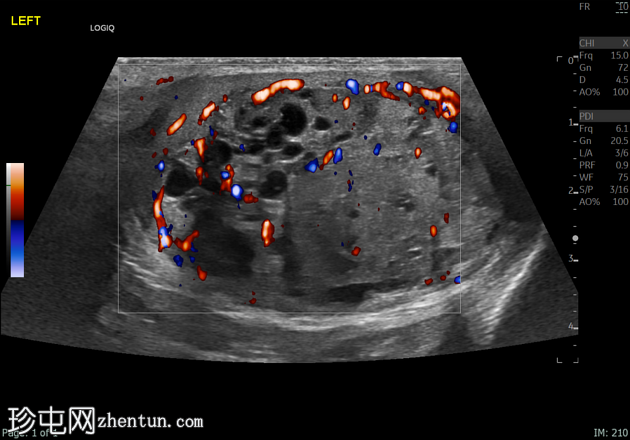

4.png

左侧睾丸肿大,体积约56 mL,可见弥漫性微结石,以及三个内部等回声病灶,伴囊性变、微钙化和明显血流信号,最大病灶大小约4.8 x 3.2 cm。